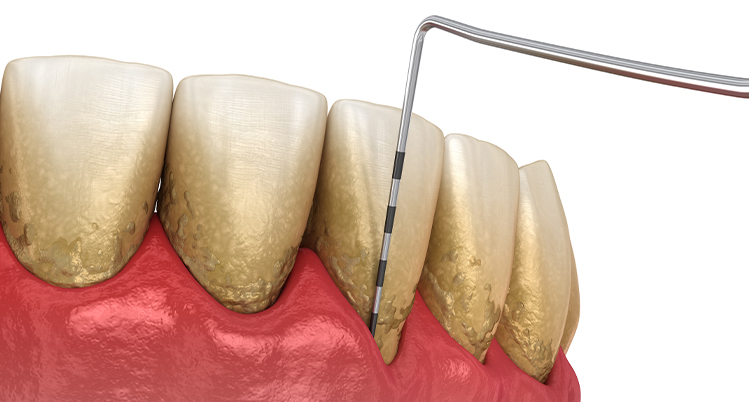

1. 歯周ポケットの深さを測定

専用の器具を使って歯ぐきの深さを測る検査です。定期健診などで行っている歯ぐきの検査と同じです。歯ぐきの深さを測るため少しチクチクと痛みを感じる方もいます。

1本の歯につき4~6か所測定します。

• 0~3mm 正常、歯肉炎、または軽度

• 4~6mm 中等度歯周炎

• 7mm以上 重度歯周炎

2. スケーリング(歯石除去)

歯科医院で行うクリーニングの中に含まれるもので、専用の機械や器具を使用して歯石を取り除きます。

歯石の表面にはざらつきがあり、プラークが溜まりやすくなるため定期的に除去しましょう。

3. SRP

(スケーリング・ルートプレーニング)

専用の器具を使って、歯ぐきの中にある汚れを除去して、歯の根っこ部分の表面を汚れの付着が起こりにくい状態に仕上げる処置です。

主に、歯ぐきの中にまで歯石が入り込んでいる中等度以上の患者さまに対して行います。痛みが強い場合は、麻酔をして行うこともあります。